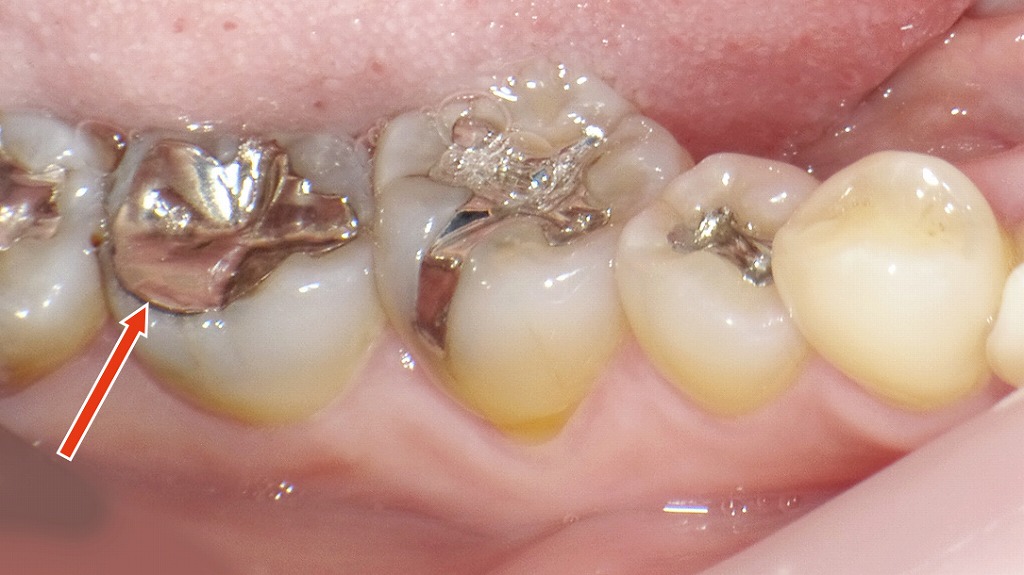

画像は下顎右側臼歯部の口腔内写真です。赤い矢印が指しているのは「下顎第2大臼歯(7番)」で、金属の詰め物(メタルインレー)が装着されています。

🔍 観察ポイント

- 修復物の種類:銀合金(金銀パラジウム合金)によるメタルインレー。咬合面全体に広がる比較的大きな修復です。

- 辺縁適合性:矢印部分、すなわちインレーと歯質の境界にわずかな隙間(マージンギャップ)が確認できます。

- 臨床的懸念点:

- 隙間部分にプラークや食片が残りやすく、2次う蝕(二次カリエス)のリスクがあります。

- 修復物の経年劣化やセメントの溶解によって、金属と歯の接合部が浮き上がっている可能性があります。

- 隣接歯の状況:近心側(6番との間)との接触点の位置関係から清掃性がやや悪化しているように見受けられます。

💡 総評

下顎7番のメタルインレーは一見問題なさそうに見えますが、境界部にわずかな隙間があるため、再う蝕や歯肉炎の原因になる可能性があります。定期的なメンテナンスや、必要に応じてセラミックやコンポジットレジンによる再修復を検討するのが望ましいです。